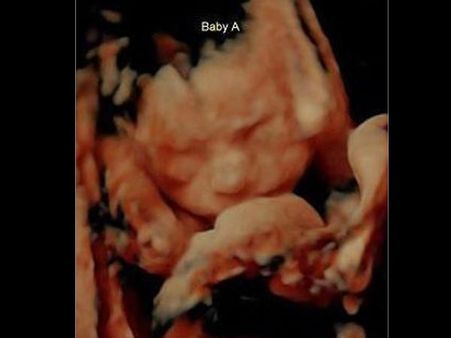

Ultrasound Photo Shows Twins Kissing!

It was a regular scan for this couple until they saw the images of the ultrasound scan clearly. It showed their twins kissing and the couple cannot wait for their arrival!

Carissa Was 25 Weeks Pregnant During The Scan…

She visited the hospital along with her boyfriend for an ultrasound scan. The couple saw an unusual thing which hardly anybody gets to see.